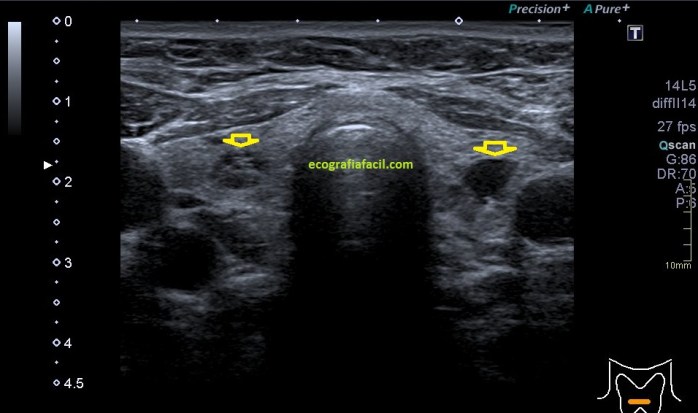

La mayoría de las exploraciones están dentro de la normalidad, este aspecto:

En algunas ocasiones podemos encontrarnos esto:

Compara la imagen 1 y la 2, grábala en tu memoria fotográfica. Ambas son unas imágenes en corte longitudinal del teste derecho de dos pacientes distintos.